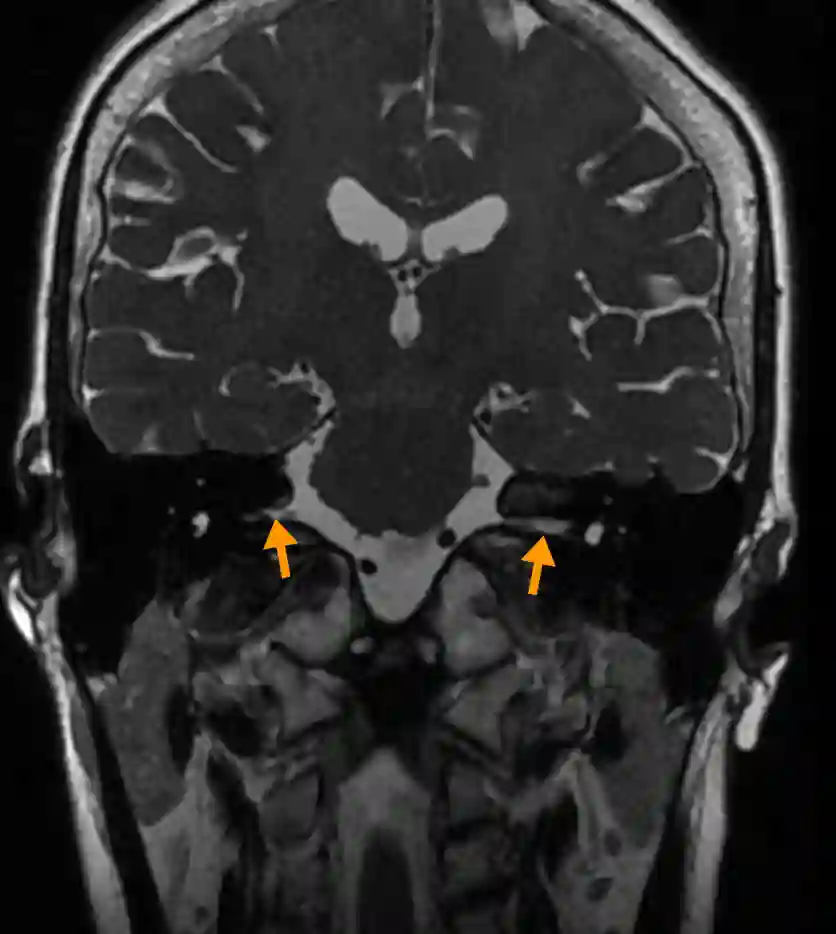

Meatus acusticus internus coronales MRT

Darstellung des Meatus acusticus internus (oranger Pfeil) in einem coronaren MRT T2 Bild des Neurokraniums.